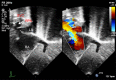

This review article will guide the reader through the basics of echocardiographic assessment of congenital left to right shunts in both paediatric and adult age groups. After reading this article, the reader will understand the pathology and clinical presentation of atrial septal defects (ASDs), ventricular septal defects (VSDs), atrioventricular septal defects (AVSDs) and patent arterial duct. Echocardiography is the mainstay in diagnosis and follow-up assessment of patients with congenital heart disease. This article will therefore describe the echocardiographic appearances of each lesion, and point the reader towards specific features to look for echocardiographically.